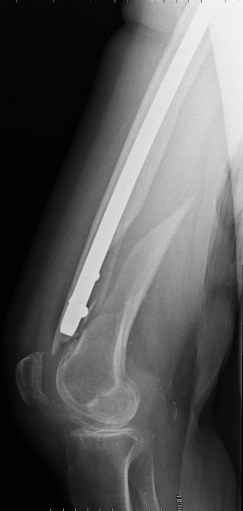

- It is an long, spiral, metaphyseal fracture – very good chance of healing (will not be any need for any bone cement…bone substitute – filler)

In my opinion the femoral bone looks osteoporotic, but no bone defect is visible to justify bone cement.

3. Retrograde nail (small diameter in large bone) does not allow for good, stable fixation (often malalignment) and early weight bearing (I have seen the locking screws and nail cutting through the distal femur into the knee joint - in osteoporotic bone, heavy persons)

4. We could treat this fracture like there is no a nail - new locking plates allow for secure fixation.... two similar cases are attached...

Gamma nail exchange may probably fit the criteria of optimal and minimal invasivness, indeed. Removal could be relatively fast due to large intramedullary diameter seen on X-ray.